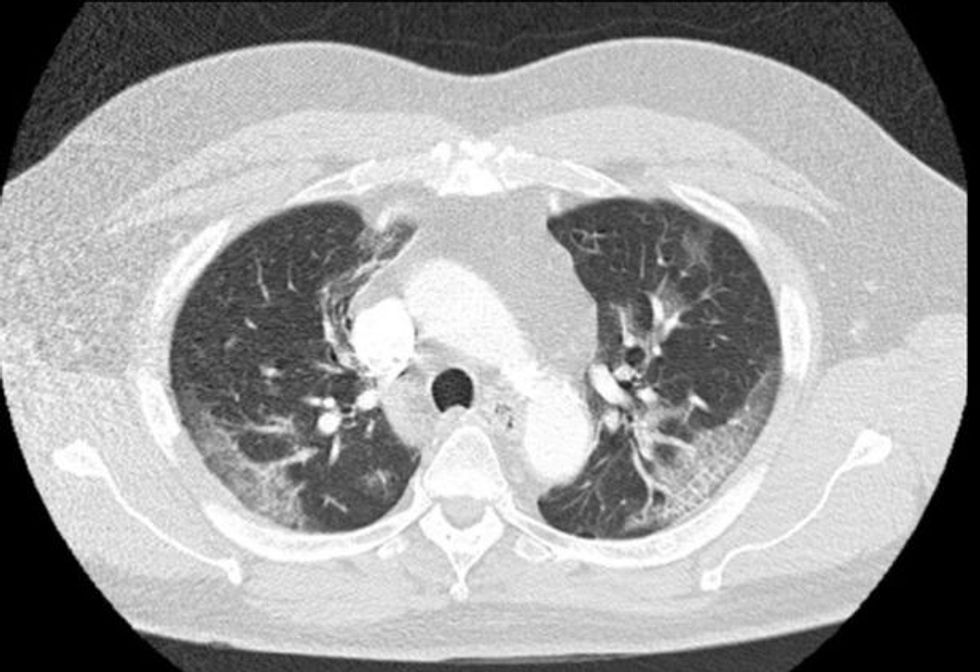

Por një skanim në mushkëri tregoi indikacionet se po luftonte me një sëmundje. Burri u vendos në një dhomë izolimi, ku u testua për coronavirus. Temperatura më vonë iu rrit në 38.4 grad celzius, transmeton Telegrafi.